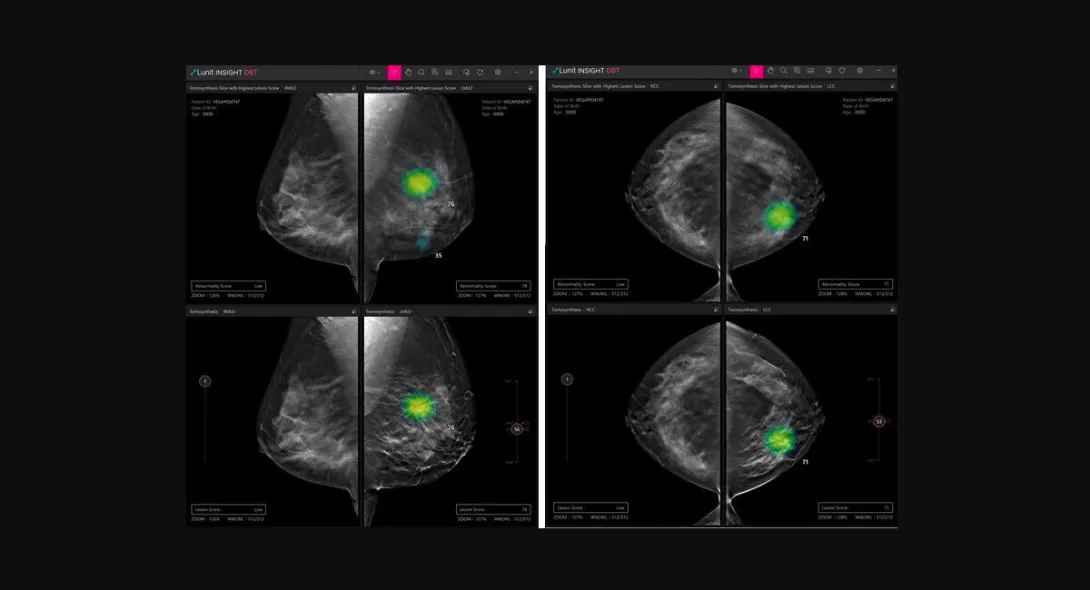

Photo courtesy of Lunit

Lunit obtains new CE mark for AI DBT solution

South Korean medical AI company Lunit has received a CE mark under Europe's latest Medical Device Regulation for its AI software for digital breast tomosynthesis (DBT) analysis.

Called Lunit INSIGHT DBT, the software solution analyses 3D images from DBT, enabling fast and accurate diagnosis of breast cancer.